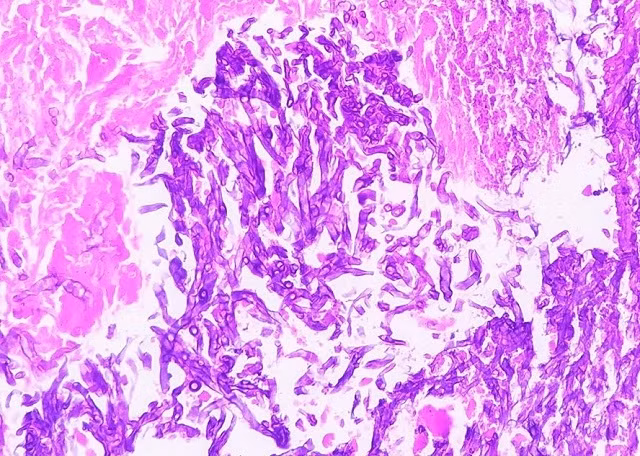

ThS Ngô Thị Thúy Quỳnh, Khoa Hô hấp cho biết, nhiều bộ phận hô hấp của người bệnh trên đã bị tổn thương viêm loét nặng, hoại tử do nấm sợi Aspergillosis xâm nhập và lan rộng. Đồng thời người bệnh cũng có tiền sử bị nhiều bệnh khác như suy gan, K tuyến giáp nên phương án điều trị khó khăn hơn, đòi hỏi sự kiên trì, thường xuyên theo sát để thay đổi phác đồ phù hợp.